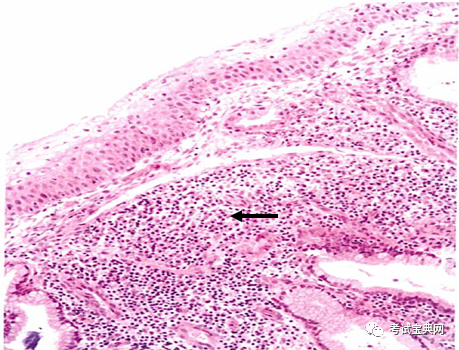

慢性子宫颈炎病理切片